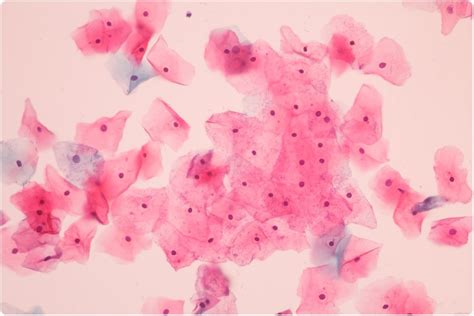

An abnormal pap smear doesn't even necessarily hint at you having precancerous cells. A routine pap exam can help women lower their risk of developing cervical cancer. A pap smear, also called a pap test, is an exam a doctor uses to test for cervical cancer in women. The papanicolaou test (abbreviated as pap test, also known as pap smear (ae), cervical smear (be), cervical screening (be), or smear test (be)) is a method of cervical screening used to detect potentially precancerous and cancerous processes in the cervix (opening of the uterus or womb) or colon. The pap test, also called a pap smear, and the hpv test both look for changes in cells of the cervix that may turn into cancer or make a woman more likely to develop cancer. Cervical cancer is a disease that can often be prevented. Early changes can be detected in the neck of the womb (cervix), which indicate that. While pap smears are supposed to be a quick test, some women still dread getting the screening.

The papanicolaou test (abbreviated as pap test, also known as pap smear (ae), cervical smear (be), cervical screening (be), or smear test (be)) is a method of cervical screening used to detect potentially precancerous and cancerous processes in the cervix (opening of the uterus or womb) or colon. A pap smear screens for cervical cancer by looking for abnormalities in the cells of a woman's cervix. Early changes can be detected in the neck of the womb (cervix), which indicate that. Since its introduction in the united states in 1941 while cervical cancer can be fatal if left untreated, the cancer typically grows slowly. An abnormal pap smear doesn't even necessarily hint at you having precancerous cells.